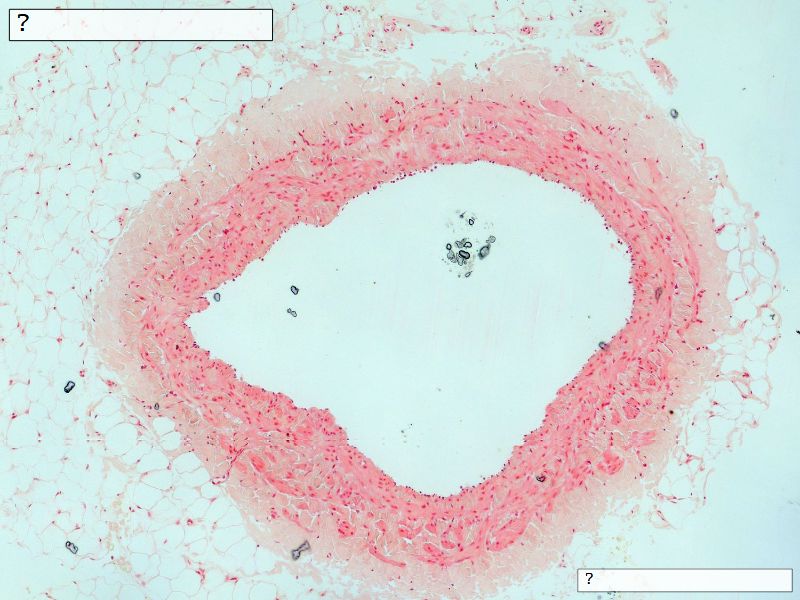

Fill in all the missing labels, and assess as you move through the slides. Answers on the down slide. It is important to do this using pen and paper, and not just glance through the images.